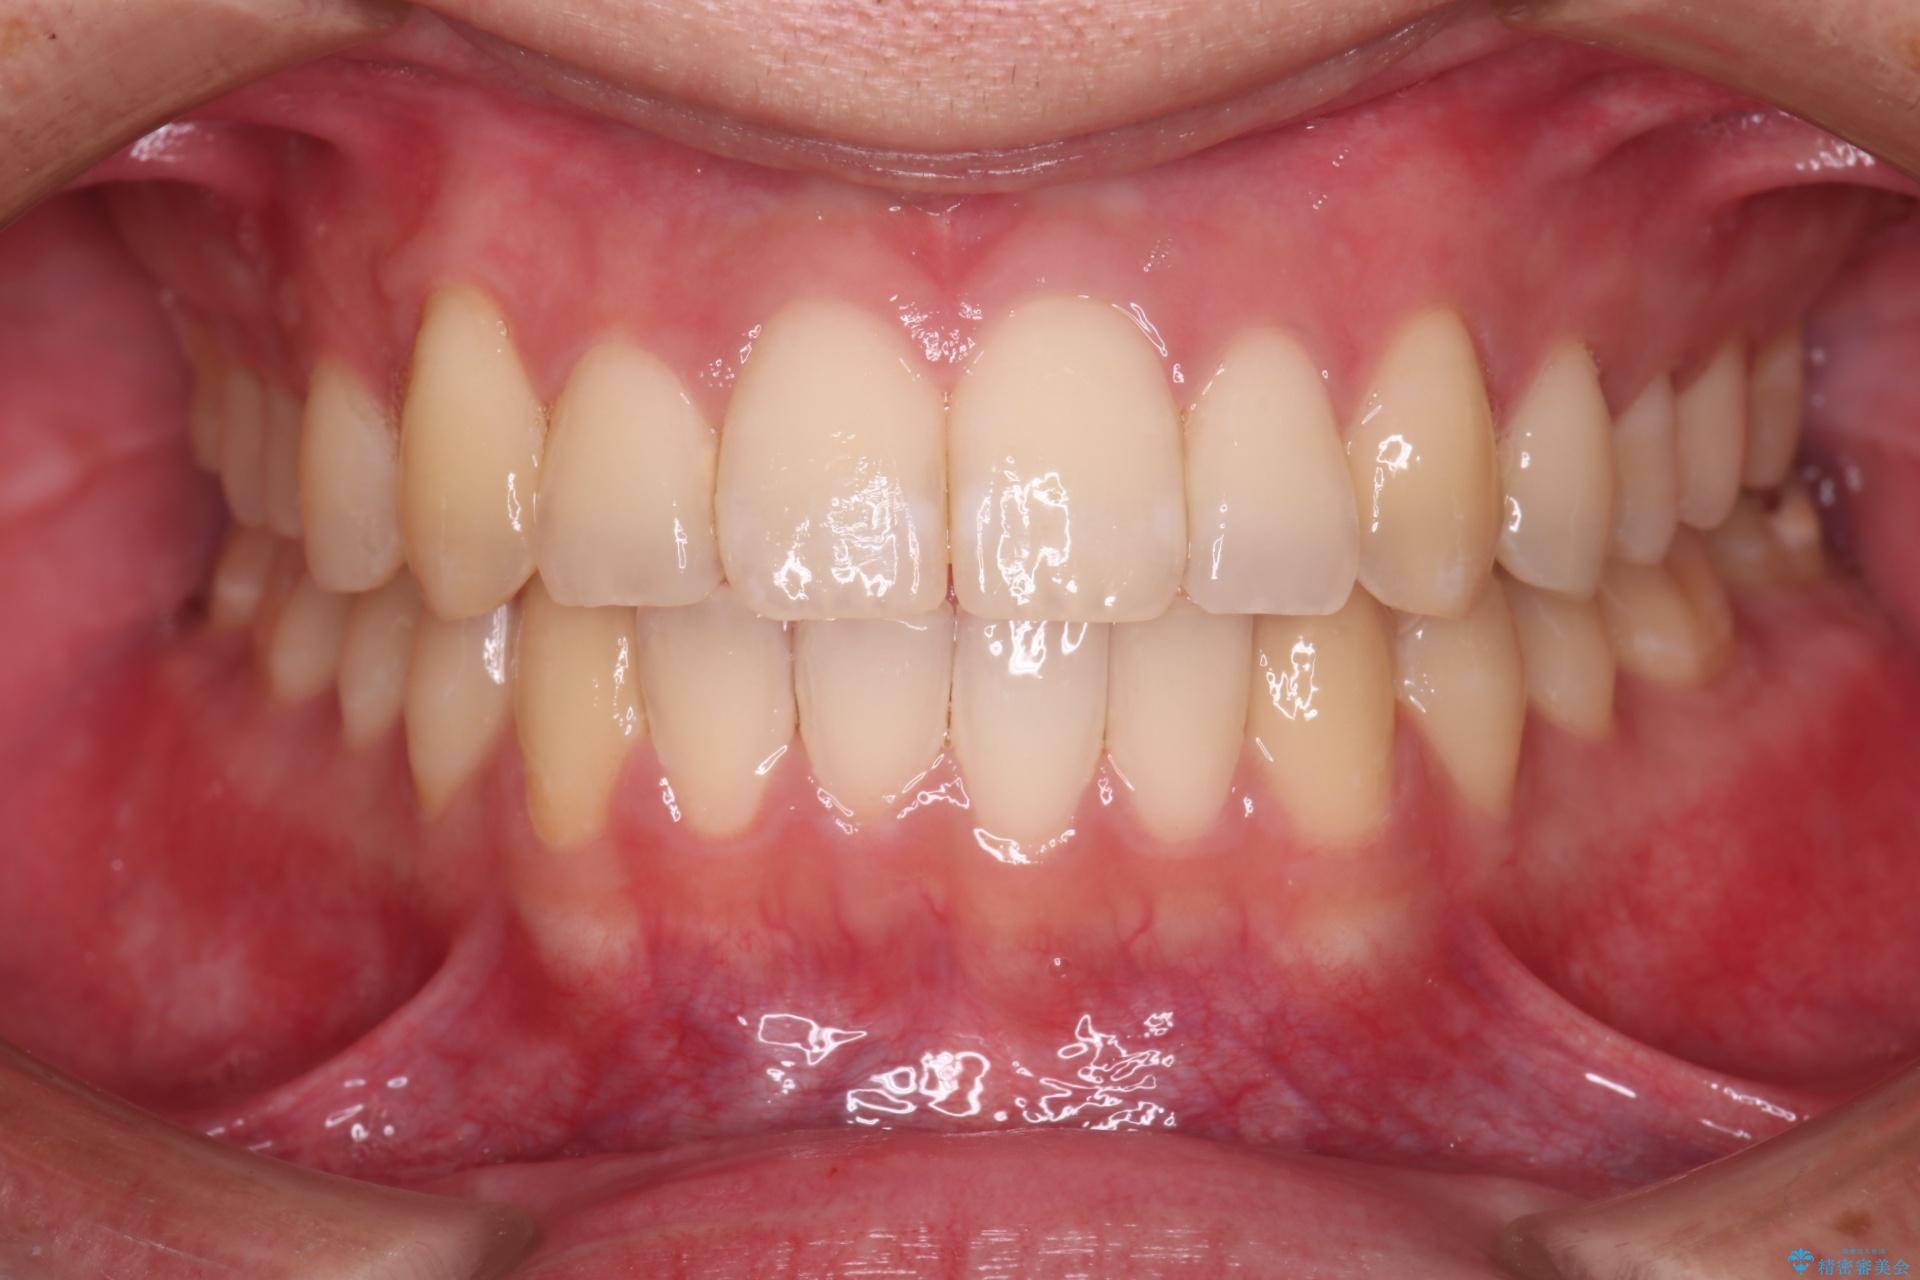

目立ちにくいクリア装置で八重歯とがたつきの改善

上の八重歯と下の歯のがたつきが気になるとご来院された患者様です。

非抜歯での治療だったため、1年半以内という短い期間で矯正を終了することができました。主訴であった八重歯とがたつきが改善され、大変ご満足いただきました。